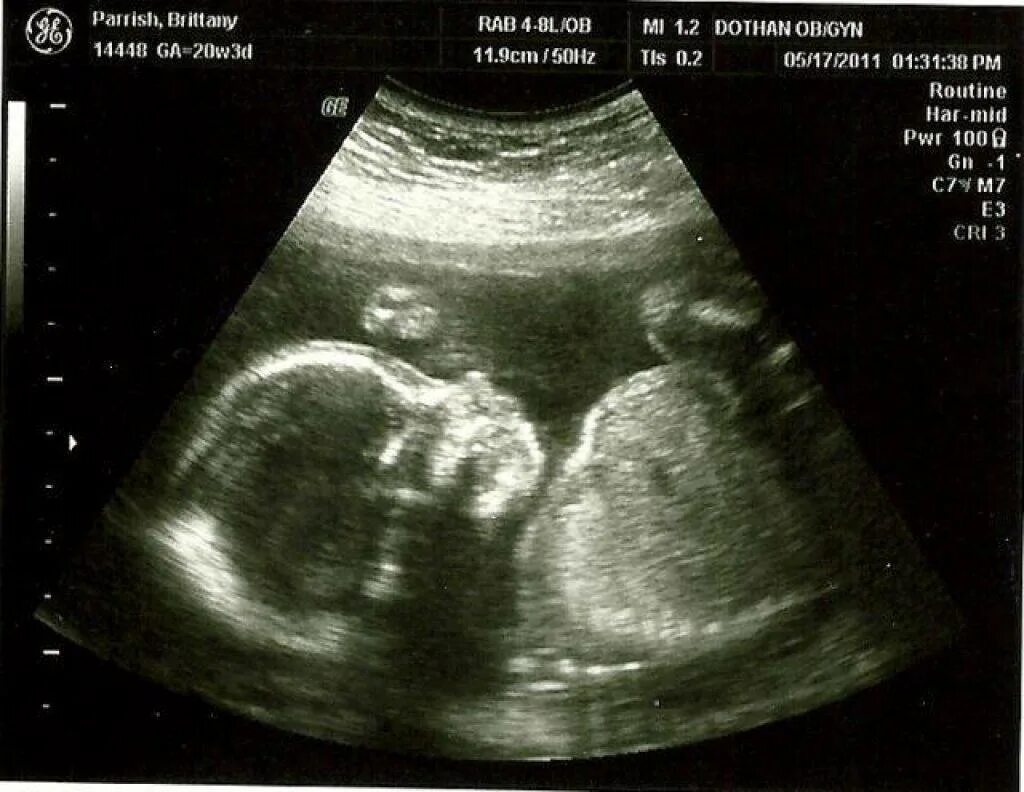

29 неделя ощущения